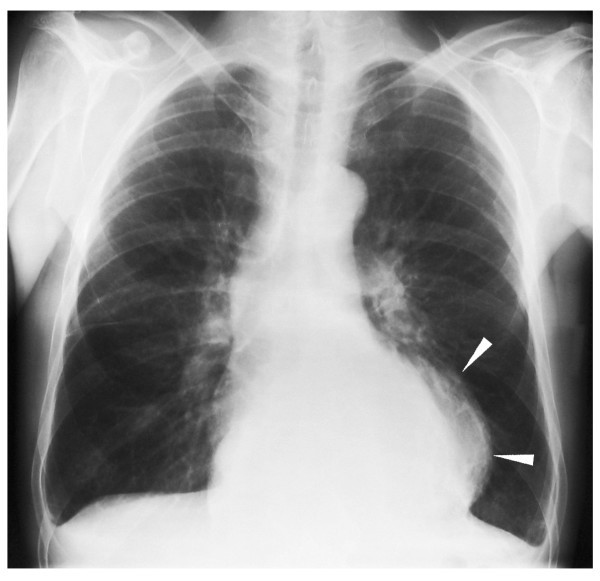

Mediastinal pancreatic pseudocyst with isolated thoracic symptoms a

From jmedicalcasereports.biomedcentral.com

Mediastinal pancreatic pseudocyst with isolated thoracic symptoms a Can A Chest X Ray Show Pancreatic Cancer each imaging modality has both its advantages and disadvantages according to the four, different aspects regarding. doctors have identified some factors that may increase the risk of pancreatic cancer, including smoking,. These look for signs of pancreatic. some endoscopes are fitted with a tiny ultrasound scanner at their tip, which can obtain pictures of structures. Pancreatic cancer. Can A Chest X Ray Show Pancreatic Cancer.